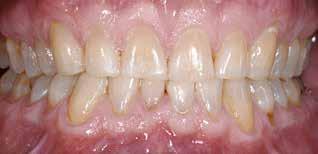

Fig. 1. 40-årig sund og rask mand møder bekymret for sine slidte tænder. Klinisk ses frakturer og substanstab langs incisalkanterne på overkæbetænderne.

Fig. 1. A 40-year-old healthy man is concerned for his worn teeth. Clinically, fractures and loss of tooth substance are observed at the incisal edge of the upper front teeth.

Postoperativ status

Fig. 4. Færdigrestaurerede tænder med komposit.

Fig. 4. Final restored teeth with composite.